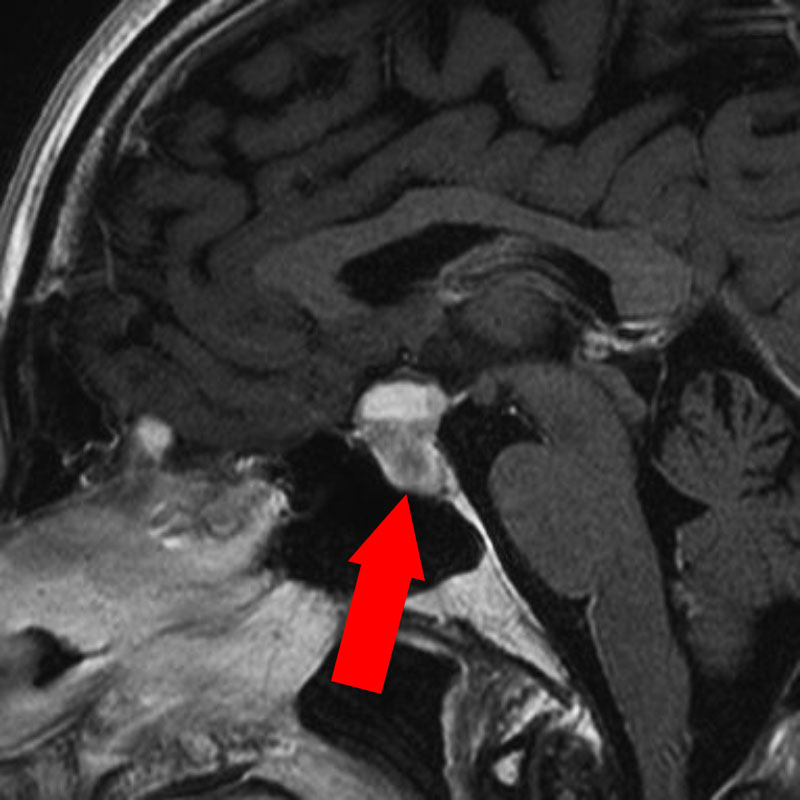

右傍矢状洞髄膜腫

頭蓋内腫瘍摘出術

No.’23_63 手術前1

No.’23_63 手術前2